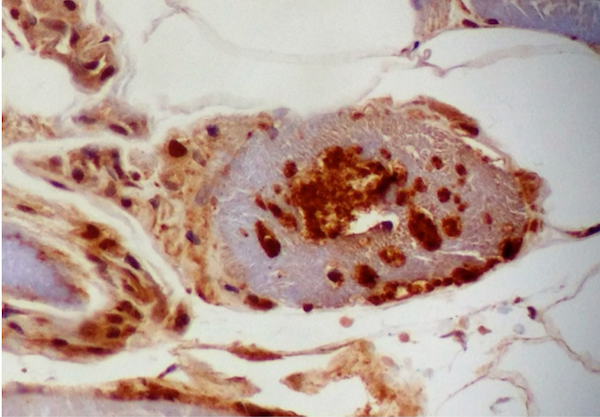

Positive stains

- Gomori trichrome shows rimmed vacuoles and can show ragged red fibers in areas

- Congo Red (amyloid) positive "apple-green" birefringence positive inclusions (Arch Neurol 1991;48:1229)

- Ubiquitin and LC3B highlight the inclusions

- Ubiquitin, B-amyloid, B-amyloid precursor protein (APP), α-synuclein, tau, TDP43, and LC3B can be seen in the inclusion bodies

- CD8+ T lymphocytes highlight the inflammatory response and infiltrate non-necrotic myofibers

- Upregulation of MHCI in myofibers (Dubowitz: Muscle Biopsy: A Practical Approach, 2013, 4th Edition)